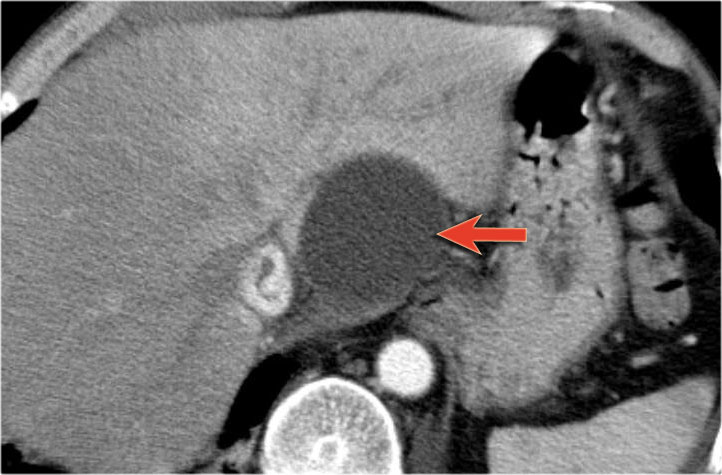

Một ví dụ khác về u nang tuyến thanh dịch (Hình).

Hình ảnh sau tiêm thuốc cản quang bên phải cho thấy tổn thương giảm tỷ trọng với vôi hóa trung tâm ở thân tụy và ngấm thuốc nhẹ của các vách ngăn.

Lưu ý rằng trên CT rất khó nhận ra bản chất dạng nang của các tổn thương này và có thể nhầm lẫn với ung thư biểu mô tuyến tụy.

MRI sẽ dễ dàng thể hiện bản chất dạng nang của các tổn thương này (hình).

Chuỗi xung T2W với xóa mỡ (fatsat) thể hiện rõ tổn thương tăng tín hiệu dạng thùy múi với sẹo trung tâm, đây là hình ảnh đặc trưng của SCN.